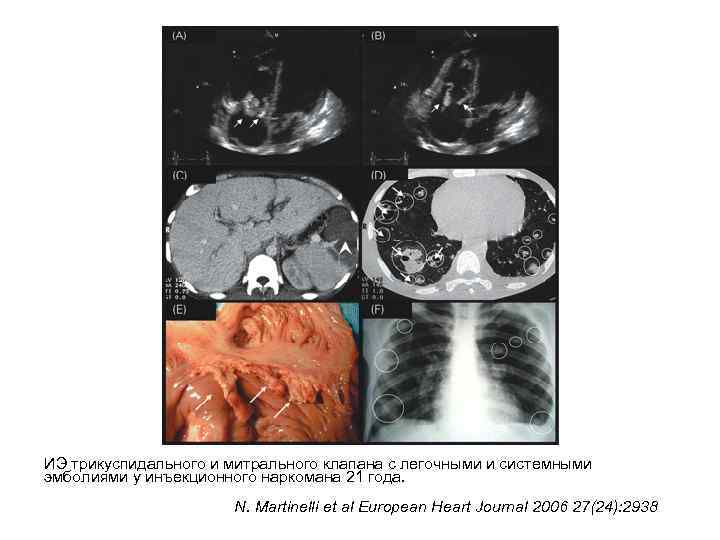

ИЭ трикуспидального и митрального клапана с легочными и системными эмболиями у инъекционного наркомана 21 года. N. Martinelli et al European Heart Journal 2006 27(24): 2938